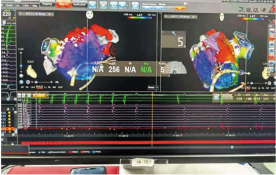

ICE指导下局麻平口封堵左心耳

此次病例患者郭某,男,61岁,因“间断胸闷、气短1月余,加重1周”之主诉入院,既往有心房颤动2年。王洪涛教授接诊患者后,综合评估患者的病情,因患者CHADS2评分大于2分,属血栓高危人群,因此建议患者行房颤射频消融+左心耳封堵一站式手术。王洪涛教授采用OCE方案,首先应用STSF导管进行高效消融,提高消融效率及安全性,更少的盐水灌注使房颤合并心衰患者亦能平安完成消融。接着采用辅助vizigo可视化可调弯鞘增加导管到位几率并大幅降低X曝光,几乎实现零射线全程消融。最后用心腔内超声(ICE)指导进行实现精准的左心耳封堵手术。该方案为房颤射频消融的新技术、新理念。